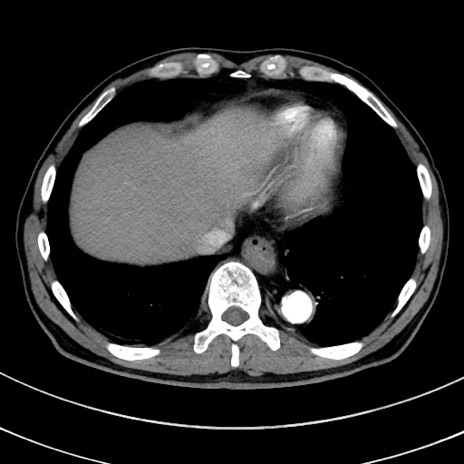

症例8(横断像)

【症例】 60歳代男性

【主訴】 黒色吐物

【現病歴】 4日前から嘔気自覚、2日前の朝食後にも嘔気あり、自分で手で嘔吐反射起こし嘔吐したところ血が混ざっていたため受診。

【既往歴】 5年前汎発性腹膜炎を伴う急性虫垂炎で手術、高血圧、前立腺肥大症、高脂血症

【身体所見】 腹部正中に手術癩痕あり 腹部平坦・軟圧痛なし膨満感あり

【データ】WBC 8400、CRP 4.54